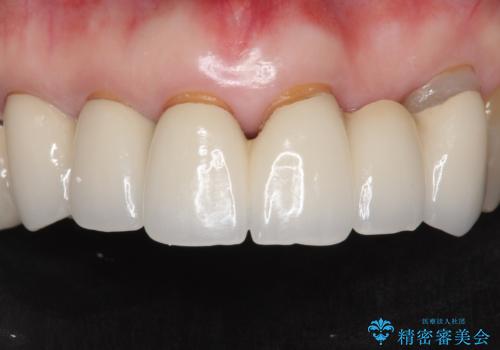

金属を使わないジルコニアセラミッククラウンの自然な仕上がりにご満足頂けました。

被せ物の種類:ジルコニアセラミッククラウン スタンダード